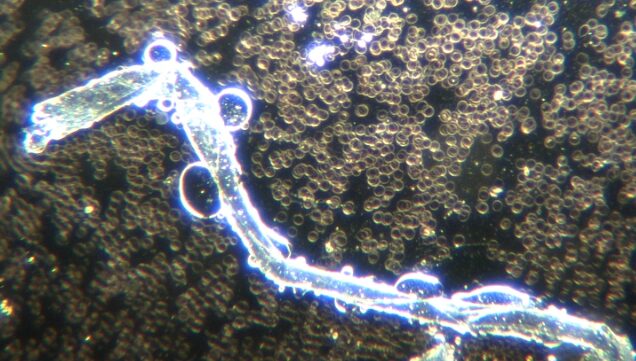

COVID19未接種患者の血液中に存在するフィラメントの自己組織化を暗視野顕微鏡で観察した複数の動画を紹介します。この非常に大きな構造は、脳卒中のような症状を含む体内の問題を引き起こす可能性があります。毛細血管は細い動脈であり、直径は約8~10ミクロンで、赤血球とほぼ同じです。このような大きなフィラメントは、毛細血管と比較して非常に大きいことが容易に理解できるでしょう。